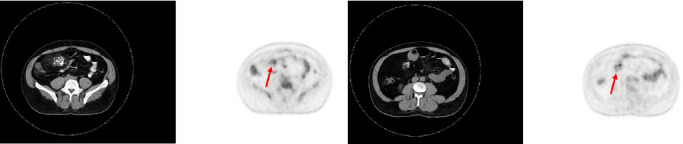

Well-differentiated liposarcomas are common retroperitoneal lesions, but exceedingly rare when primary to the small bowel mesentery, with only a handful of cases reported in the literature. Presented is a patient with a primary mesenteric well-differentiated inflammatory liposarcoma with mucosal extension at high risk for misdiagnosis. A broad differential diagnosis with careful histopathologic observation, ancillary immunohistochemical studies, and fluorescent in situ hybridization for MDM2 amplification are key to make a correct diagnosis. This is especially true if such a lesion was first noted in the lamina propria on histopathology from an endoscopic mucosal biopsy.

Abstract Image